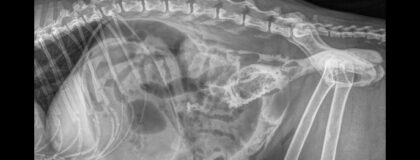

Dieses vetinar der Kursreihe Strahlenschutz für TPA beschäftigt sich mit Kontrastuntersuchungen des Magen-Darm-Trakts und des Harntrakts. Zusätzlich werden mögliche Stolpersteine am Röntgenbild besprochen, sowie auf Artefakte im digitalen Röntgen eingegangen. Speziell auf Tiermedizinische Praxisassistentinnen/Praxisassistenten (TPA) und Tierpflegerinnen/Tierpfleger (TP) zugeschnittene Online-Fortbildung im Bereich Strahlenschutz gemäss den Richtlinien der Schweizer Ausbildungsverordnung. Dieses wichtige Weiterbildungsangebot entsteht in enger Zusammenarbeit mit der Gesellschaft Schweizer Tierärzte (GST).